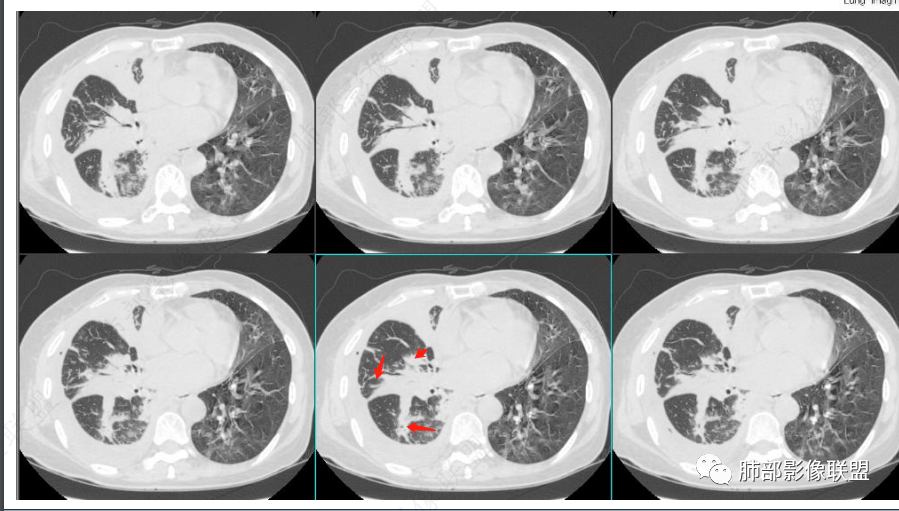

为啥给的视频支气管扩张明显啊!似乎有树芽征,如果确实是树芽征,结核要考虑。

那就结核放首位,鹦鹉热其次;支气管、树芽征符合;还是要警惕结核,肺链不支持。

单纯PPT的图像我考虑鹦鹉热。但是给的视频,明显支气管远端扩张。

这也是我判断失误的原因之一:树芽征

重建后就是血管束增粗

我以为树芽征,其实是中轴间质增厚

没看清楚,只看到表面,考虑小气道结节,那些是支气管扩张+空洞,所以考虑结核,其实两点都错了,谢谢赖老师。

应该要二元.看这样的支气管。